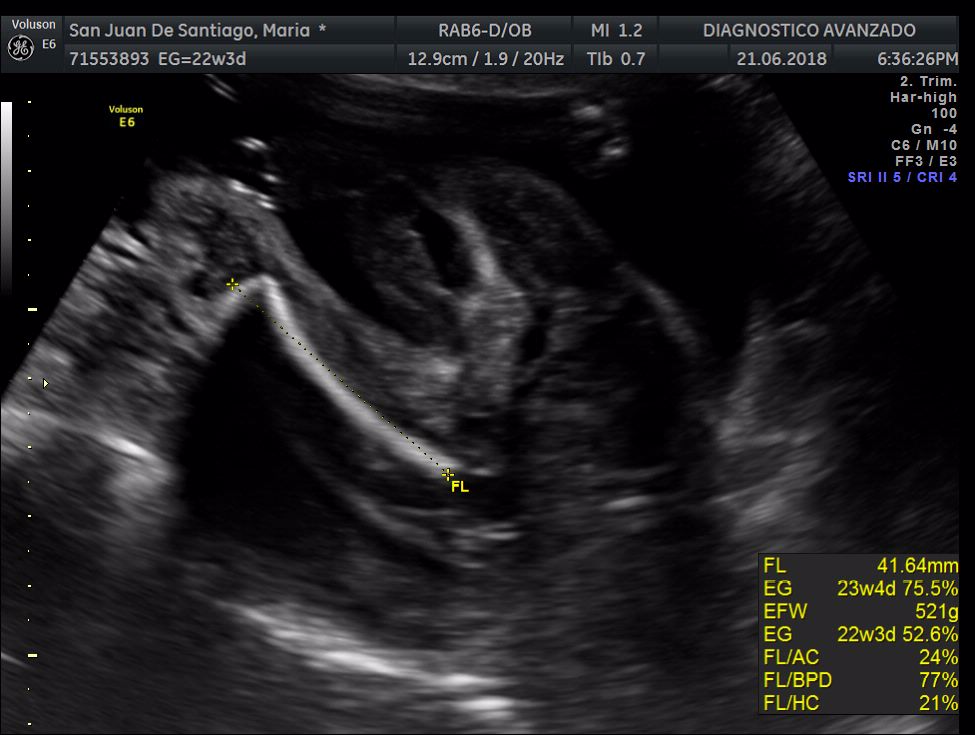

¡Hola a todos! Hoy hemos ido a hacer la tradicional ecografía 3D de la niña, os dejamos todo el material (aunque es un poco demasiado).